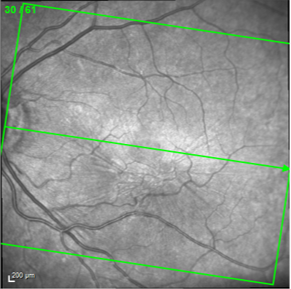

Il s’accompagne ensuite d’un OCT qui permet de voir la traction vitréenne, la présence d’une membrane et de mesurer l’épaississement maculaire.

Enfin un fond d’œil dilaté sera également réalisé par l’ophtalmologiste pour visualiser directement la traction et rechercher des complications périphériques du décollement du vitré. La vision du patient reste floue quelques heures après l’examen.